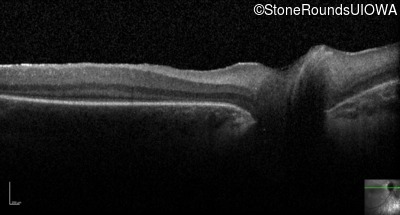

Optical Coherence Tomography - Right -

No Light Perception

Optical Coherence Tomography - Left -

Light Perception